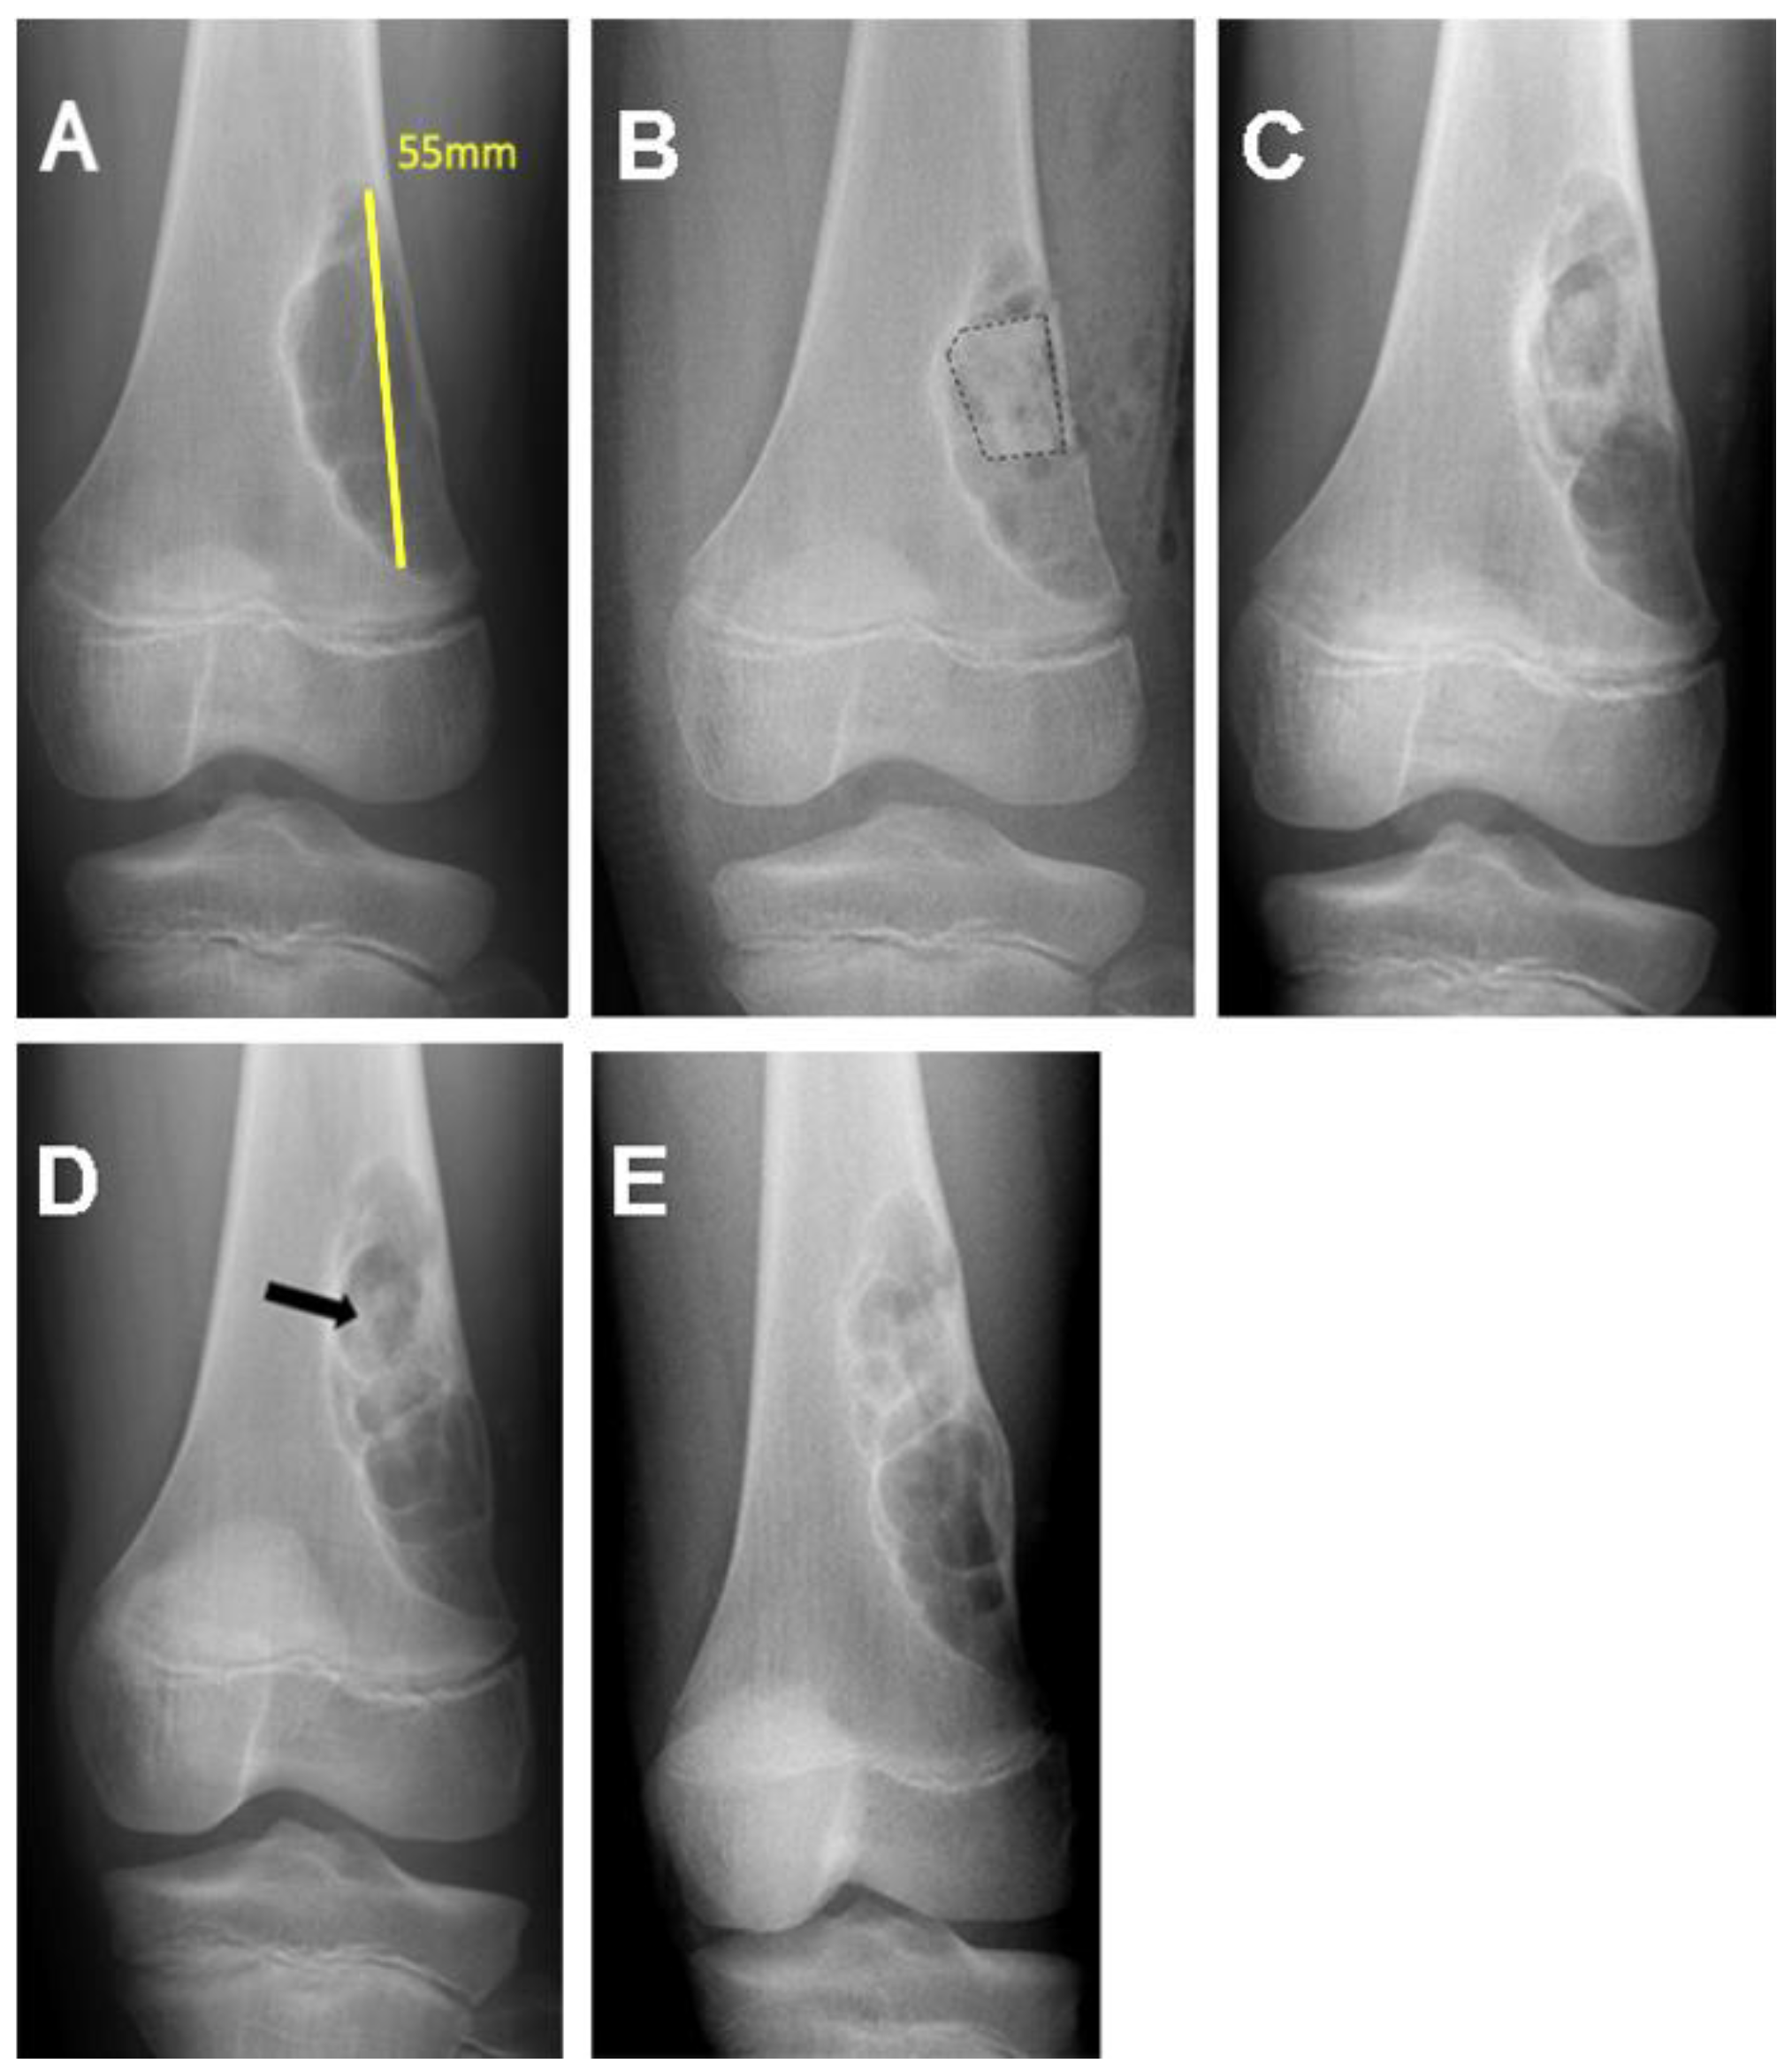

| 17/M/11 | Distal femur | Nonossifying fibroma | 7.11 |